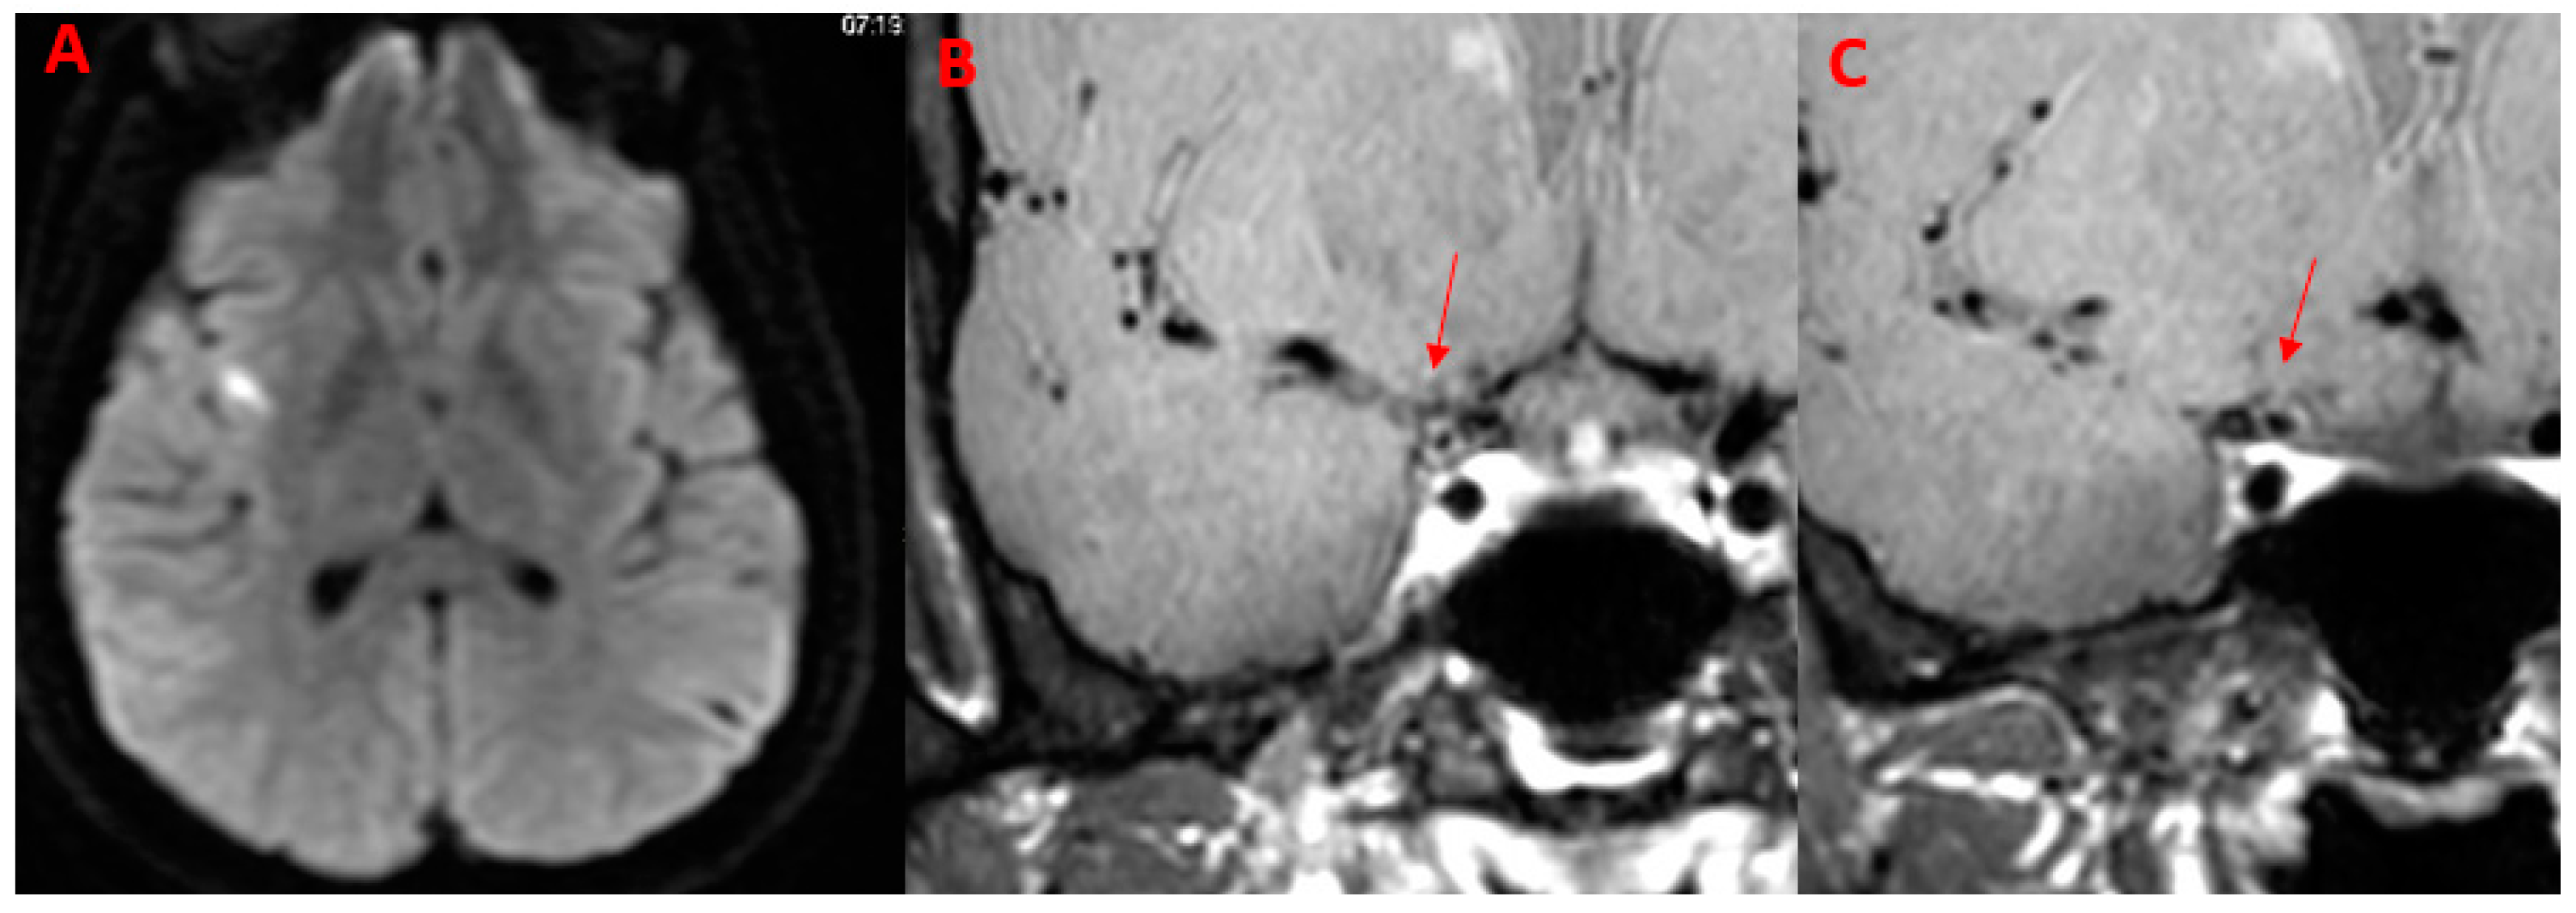

| 50Y, F | 1 | Present | Present | Parietal lobe | MCA (M1) | None | Present | Supratentorial, subtentorial |

| 52Y, F | 1 | Present | Present | Multiple subcortical in MCA territories | MCA M2 | None | Absent | // |

| 53Y, M | 1 | Present | Present | Fight corona radiata | ICA | ACOP | Present | Supratentorial |

| 63Y, M | 1 | Present | Present | Multiple Subcortical in ACA, MCA Territories and Pons | ACA (A2) | None | Present | Supratentorial, subtentorial |

| 29Y, F | // | Absent | Absent | No | ICA | ACA (A1), MCA (M1) | Absent | // |

| 32, M | // | Absent | Present | No | ICA | ACA (A1), MCA (M1) | Absent | // |